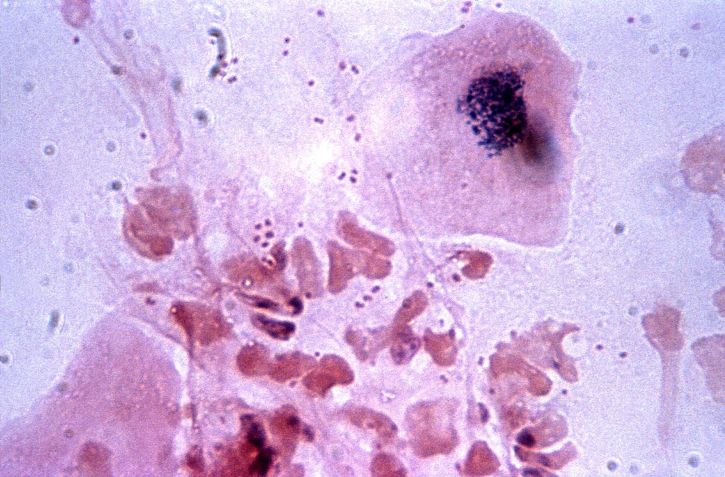

백혈구는 전체 혈구의 약 1% 이하를 차지하는 세포로,

우리 몸을 외부의 바이러스나 세균으로부터 보호하는 면역 기능을 수행합니다.

백혈구는 림프구, 호중구, 호산구, 단구, 호염기구 이렇게 다섯 가지로 나뉘는데,

각기 다른 역할을 하며 우리 몸을 지켜요. 성인의 정상적인 백혈구 수치는 5000~10000개입니다.